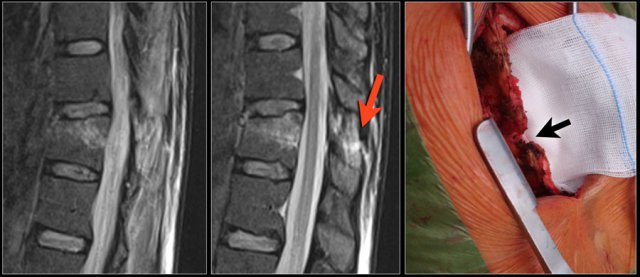

The images are of a patient with a typical bamboo spine as a result of ankylosing spondylitis.

After a fall on his back no fracture was seen on the x-rays.

However the CT shows a thin fracture line through the anterior side of the vertebral body and also through the spinous process.

Continue with the MR-images.

Look at the images.

What are the findings?

Then scroll to the next images.

The findings are:

1. Vertebral bodies show marrow edema as a result of a fracture.

2. Torn flaval ligament (yellow arrow).

3. Fractures through the posterior elements (red arrows).

The TLICS-score is high, because there is distraction and injury to the PLC.